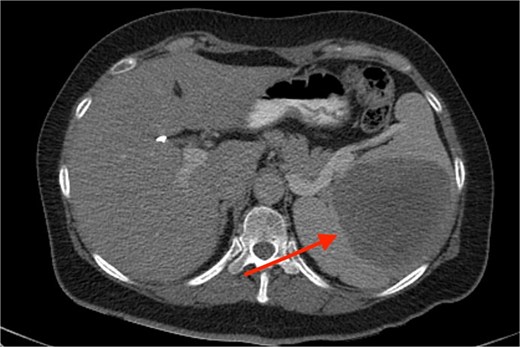

A 53-year-old Caucasian White female reached for surgical consultation after suspicious imaging findings of the spleen. Her past medical history is clear except for symptomatic cholecystectomy 4 years prior. During preoperative ultrasound guided evaluation, a 2 cm abnormal mass is identified in the splenic parenchyma. After recovery from the cholecystectomy, persistent symptoms of dizziness and fatigue prompted evaluation with a complete blood count, which revealed: hematocrit level of 32%, and MCV of 60.7 fl. Because of the previous ultrasound finding, a computer tomography scan is ordered, and the splenic mass is measured at 5 cm of maximal diameter. The patient’s symptoms resolved but presented again 2 years after, and repeat CBC and computed tomography (CT) were conducted, resulting in a hematocrit level of 29% and the mass measured at 10 cm of maximal diameter (Fig. 1). Positron emission tomography revealed increased fluorodeoxyglucose (FDG) uptake of the spleen which raised concerns for surgical intervention. Therefore, the patient was ruled as a candidate for splenectomy. Laparoscopic removal was chosen but due to excessive hemorrhage the operation was converted to open surgery. The spleen was removed and the patient recovered after 5 days of hospitalization. Monthly postoperative blood checks showed a gradual increase and stabilization of the hematocrit at 38%, 6 months after surgery. At the 1-year follow-up with a positron emission tomography - computed tomography (PET-CT) scan, no signs of malignancy were observed. Eighteen months after surgery the patient has completely recovered and has no symptoms of recurrence.

As far as diagnostic modalities used, CT or MR scan are the most widely preferred. Many SANT lesions are described as exhibiting the “spoked wheel” pattern. This “spoked wheel” has been shown on detailed radiological and pathological findings, which is equivalent to the classic central stellate fiber interstitial fibrillar nodules isolated nodules [6].